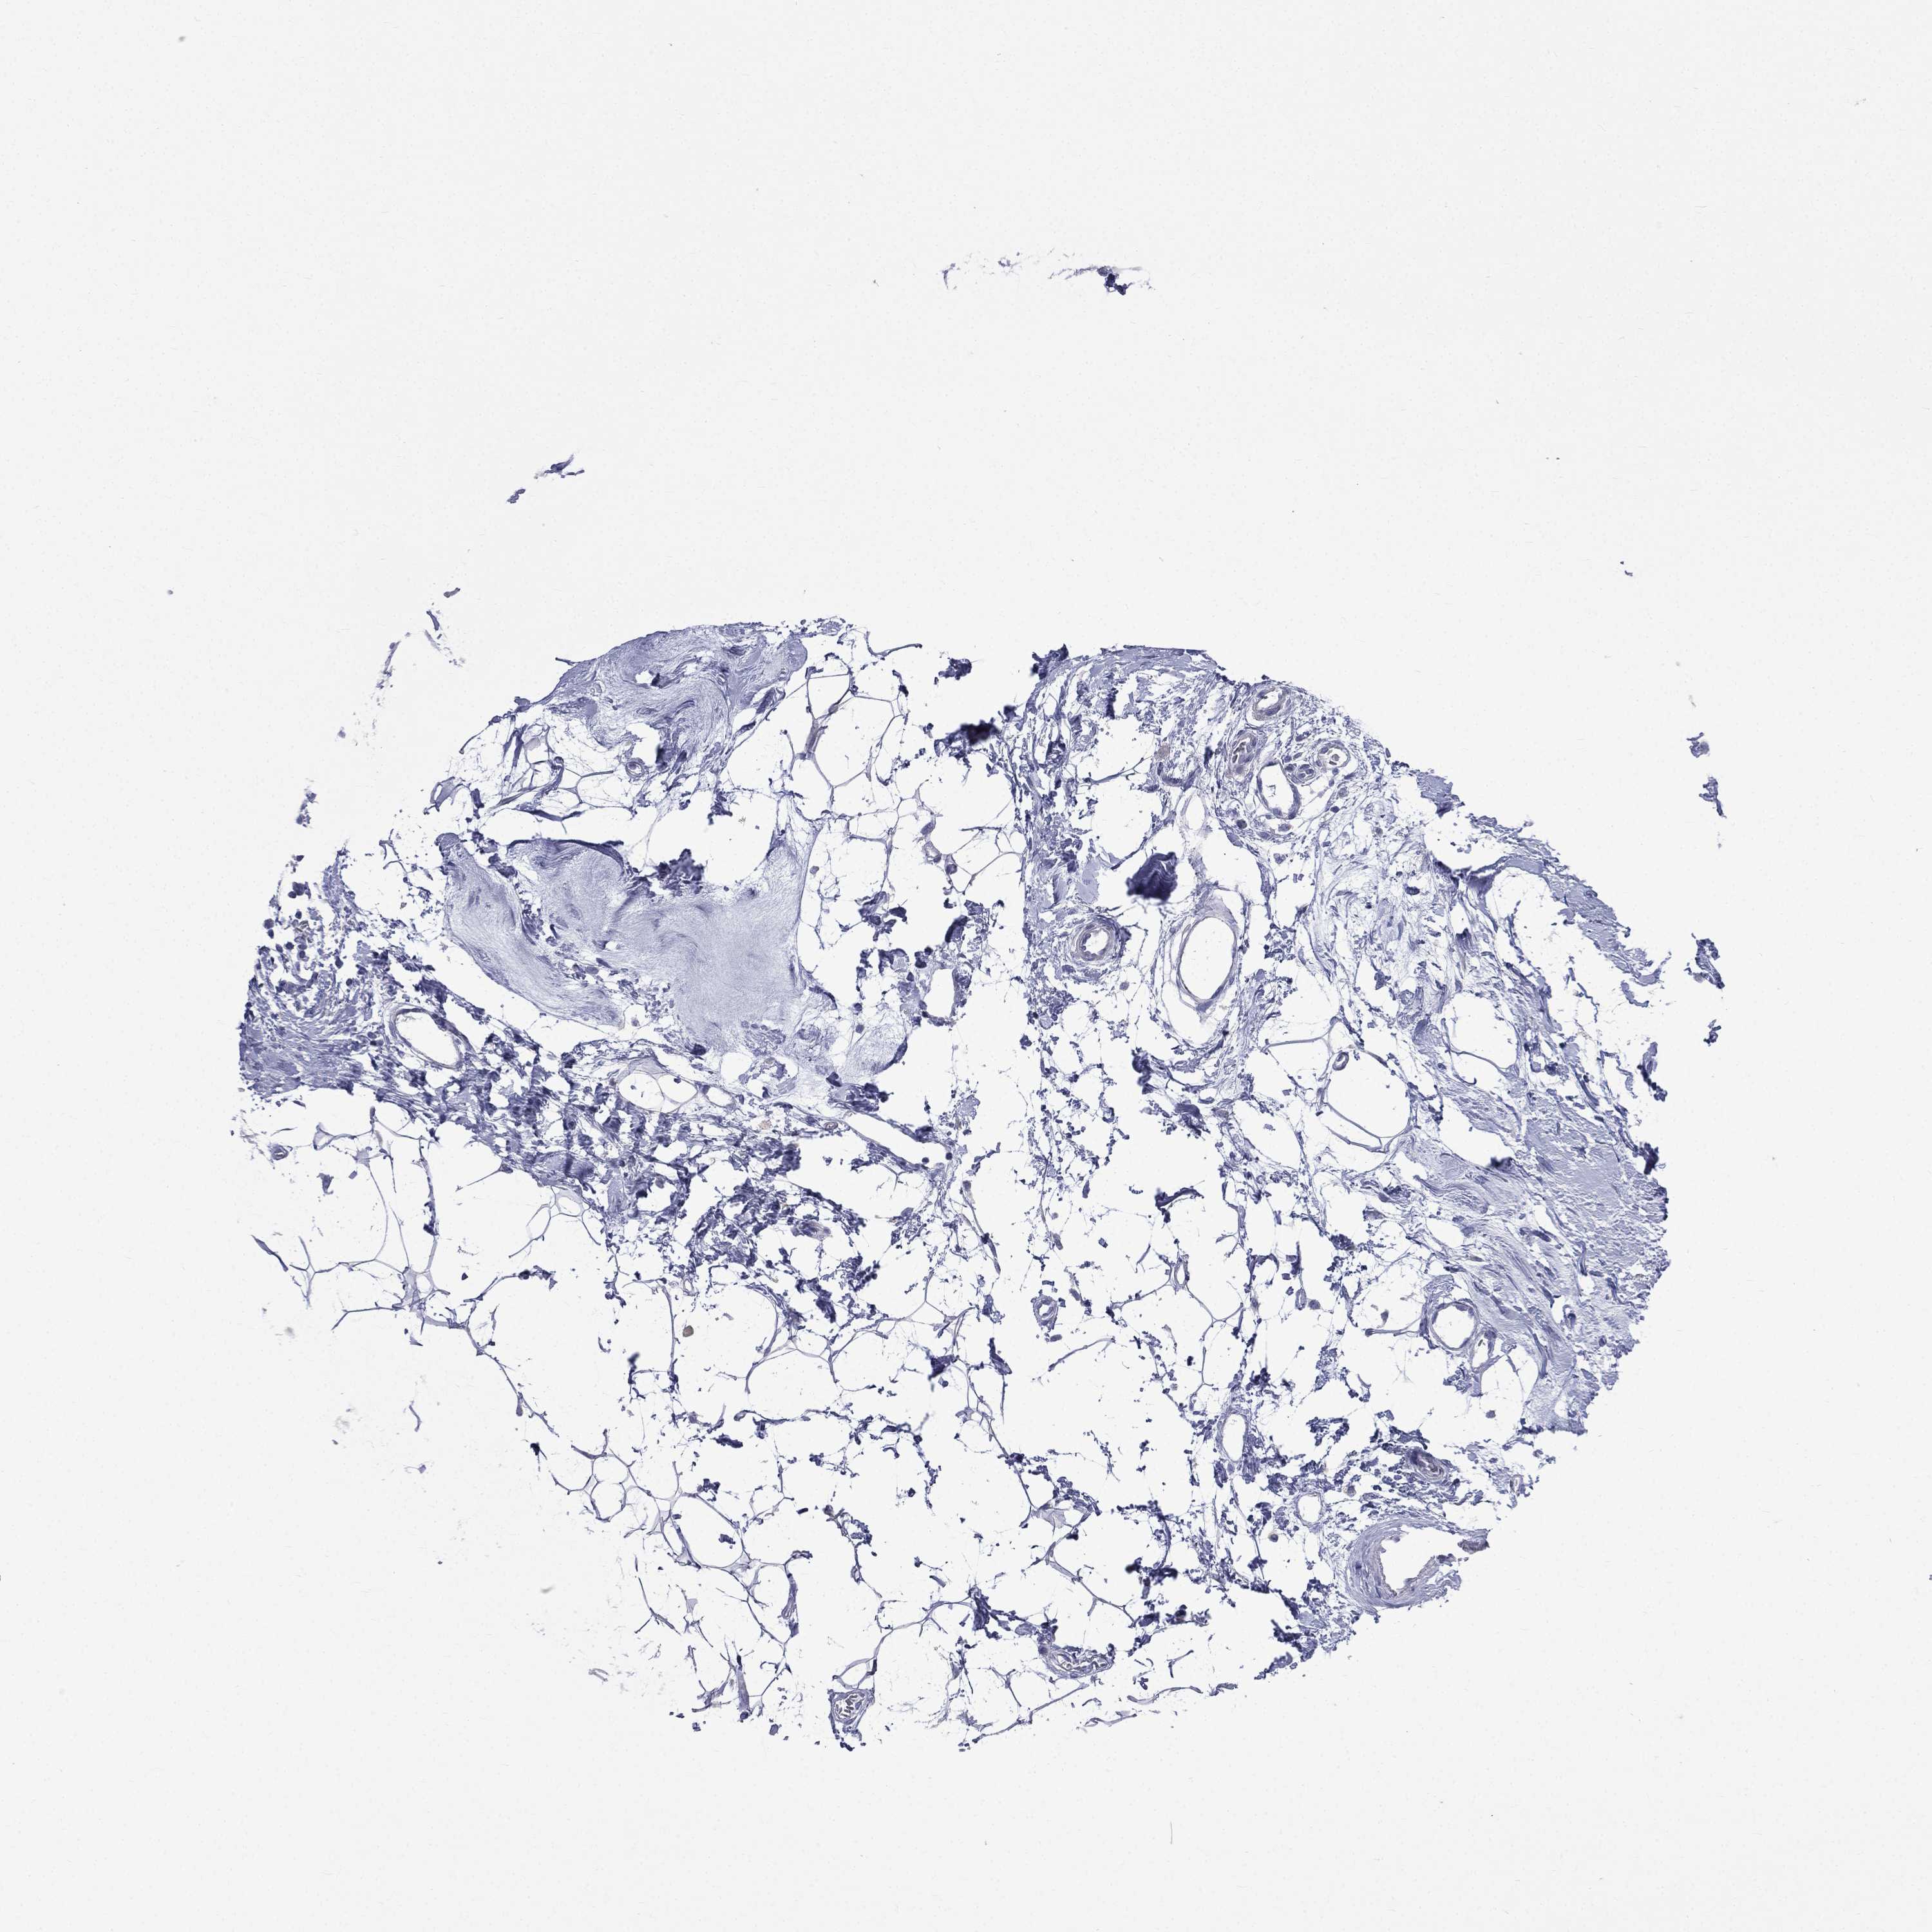

CANCER BREAST CANCER Show tissue menu

BRCA TCGA BRCA VALIDATION PROTEIN EXPRESSION

ANTIBODIES

AND

VALIDATION